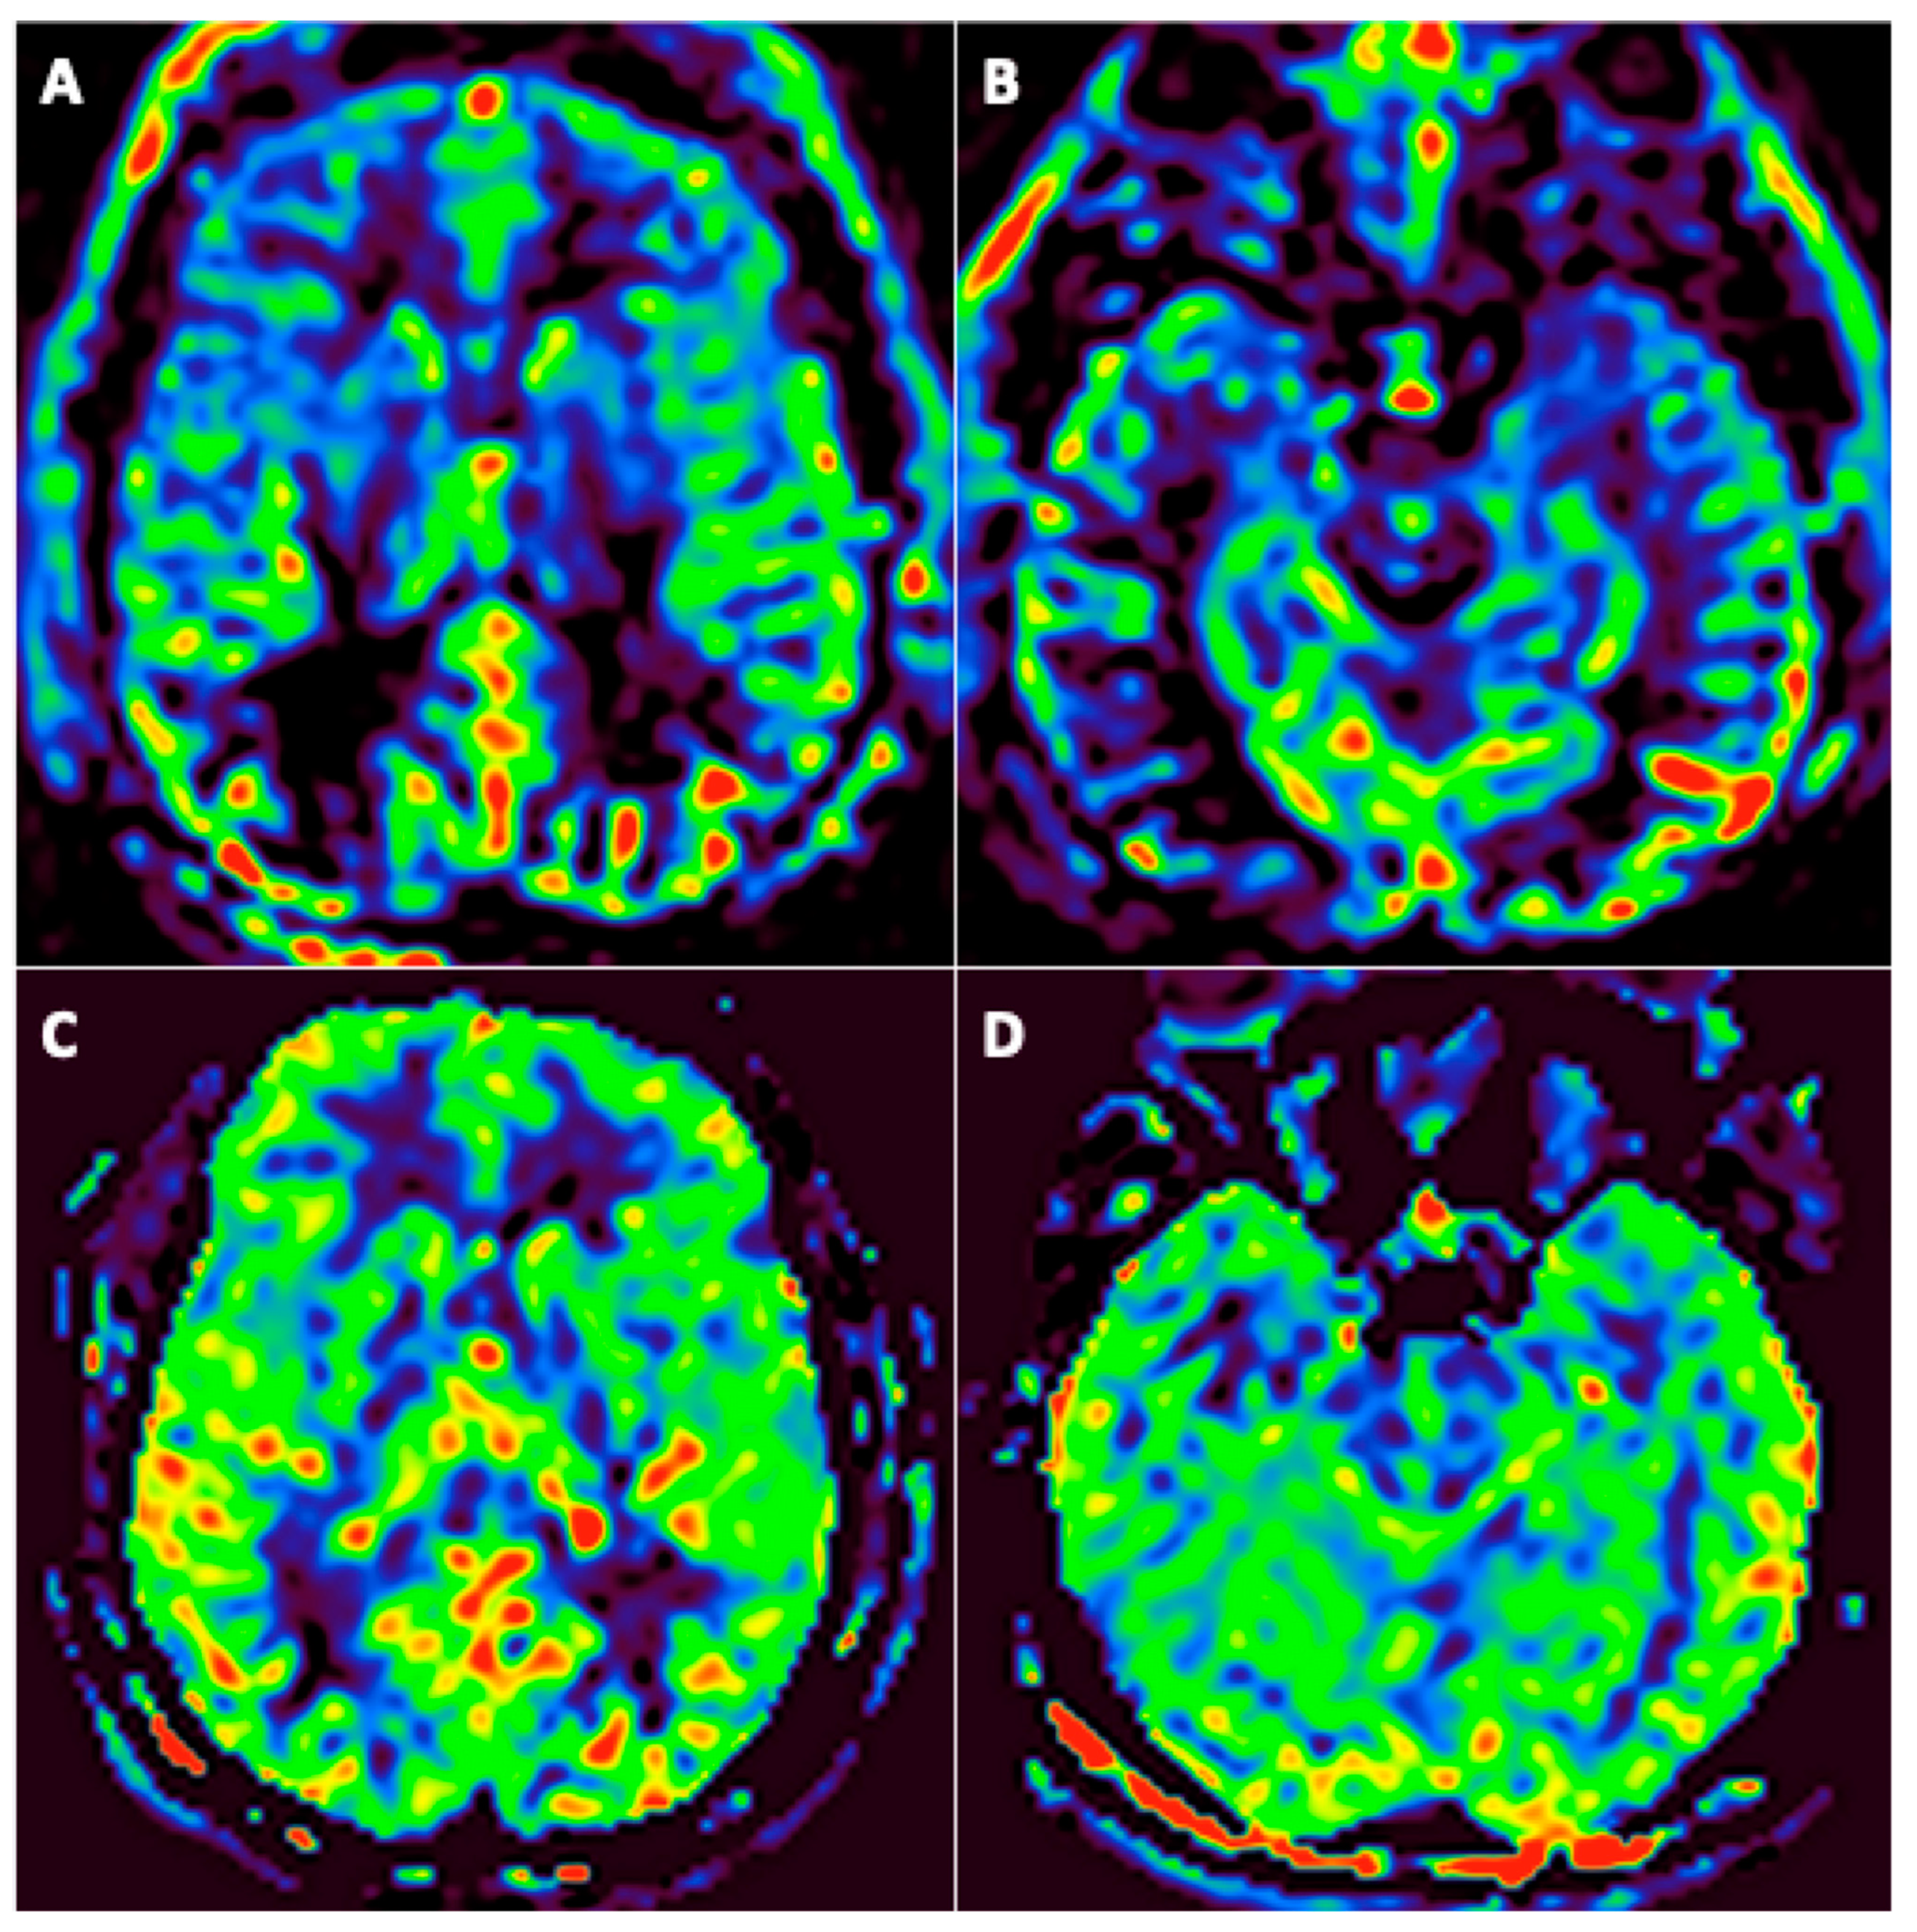

3.3. FDG-PET/CT Findings

- -

- One patient had PET in the acute phase;

- Twenty-three patients had PET at three months (among them, 12 underwent a second PET at six months);

- One patient underwent PET at six months.

| #2 | NR | Colliculus’s hypermetabolism; Left medial temporal hypometabolism | Unchanged |

| #3 | NR | Colliculus’s hypermetabolism; Bilateral temporal polar and insular lobes (L > R) hypometabolism | Unchanged |

| #4 | NR | Colliculus’s hypermetabolism; bilateral temporo-insular and right centro-opercular region hypometabolism | Colliculus’s hypermetabolism; Improvement of hypometabolism |

| #5 | Colliculus’s hypermetabolism; Left medial temporal hypometabolism | Colliculus’s hypermetabolism; Left medial temporal hypometabolism | Regression of colliculus’s hypermetabolism; Stability of left medial temporal hypometabolism |

| #10 | NR | Bilateral temporo-insular lobes and middle cerebral artery territories hypometabolism (R > L) | Bilateral medial temporal hypometabolism |

| #11 | NR | Bilateral temporo-insular and parietal lobes hypometabolism | NR |

| #12 | NR | Left medial temporal hypometabolism | NR |

| #13 | NR | Bilateral temporo insular hypometabolism | NR |

| #14 | NR | Left medial temporal hypometabolism | Unchanged |

| #15 | NR | Bilateral temporo insular hypometabolism | NR |

| #16 | NR | Colliculus’s hypermetabolism; Bilateral temporo insular hypometabolism (L > R) | Left medial temporal hypometabolism |

| #17 | NR | Colliculus’s hypermetabolism; Medial temporal and right thalamus hypometabolism | NR |

| #18 | NR | Colliculus’s hypermetabolism | No abnormalities |

| #19 | NR | Bilateral temporal hypometabolism | NR |

| #20 | NR | Colliculus’s hypermetabolism | No abnormalities |

| #21 | NR | Left medial temporal hypometabolism | Unchanged |

| #22 | NR | Colliculus’s hypermetabolism; Bilateral temporal hypometabolism | Unchanged |

| #23 | NR | Colliculus’s hypermetabolism; Bilateral temporal hypometabolism | NR |

| #24 | NR | No abnormalities | No abnormalities |

| #26 | NR | Left medial temporal hypometabolism | NR |

| #27 | NR | Colliculus’s hypermetabolism; Bilateral temporal hypometabolism bitemporal | NR |

| #28 | NR | Left colliculus hypermetabolism;^1Right fronto-temporo-insular and left thalamus hypometabolism | NR |

| #29 | NR | Colliculus’s hypermetabolism; Bilateral parietal and temporal hypometabolism | NR |